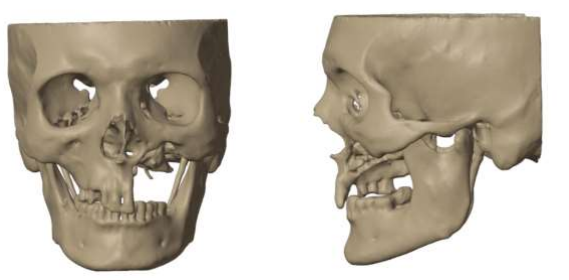

The patient underwent CT scan and subsequently the DICOM data was sent to the engineering team. The virtual planning was done using MIMIC software for segmentation and BLENDER software for final designing        (Figure 2). The models were sent for FEA analysis to pass a set of standardised protocols in which nodal points were used to solve equation for stress with different colors representing load distribution for visualization purposes with blue signifying minimum stress and red signifying maximum stress. The implanted maxilla was subjected to biting and chewing simulations with a compressive force of 300 N and the von Misses stress on the implant was measured to be 43.521 MPa, which was much lesser than the allowable limit of 830 MPa thus indicating the PSI design to be biomechanically and functionally stable (Figure 3). An SLA printer was used to print a polymer resin prototype for final consultation with the operating surgeon before metal printing (Figure 4). The powder size was kept 30 microns with a layer thickness of 20-80 micrometer. Scanning speed was kept 4.5 meter/second with the laser power being 100 W. The transitional fillet radius of the implant was 1.5mm with the bending stress calculated being 107.14 MPa. “I style” fixation plate was adopted over the “L style” as it is the only configuration possible in the maxilla and staggered countersink holes with an angulation of 45 degrees were used. The implants were printed using Ti6Al4V titanium alloy and tested for accuracy using GOM software which is used for generating report for surface analysis and deviation with a 3D scanner being used to scan the finished 3D printed model to compare the surface deviations. Maximum deviation of 0.29 mm was observed for the maxillary PSI which was lesser than the acceptable limit of +/- 0.4 mm as per quality standards (Figure 5).

Figure 4: PSI design

Figure 4